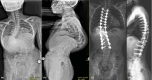

Background: Dystrophic neurofibromatosis type I (NF1) kyphoscoliosis presents unique challenges for corrective spinal surgery due to anatomical abnormalities. To compare the radiographic and clinical outcomes of dystrophic neurofibromatosis type 1 (NF1) kyphoscoliosis patients undergoing three-column osteotomy (3CO), halo-gravity traction (HGT), or posterior column osteotomy (PCO) and to evaluate their efficacy and safety in this cohort, different treatment strategies and their associated complication rates warrant further comprehensive investigation.

Methods: Dystrophic NF1 kyphoscoliosis were divided into 3CO, HGT, and PCO groups based on the surgical strategy. Radiographic parameters were measured preoperatively, postoperatively, and at each follow-up. Intraoperative and postoperative complications were recorded for each patient, and patient-reported outcomes were assessed using the Scoliosis Research Society-22 (SRS-22) questionnaire. Differences among the three groups were analyzed.

Results: A total of 9 patients were included in the 3CO, 22 in HGT group, 95 in PCO groups, respectively. Significant differences among the three groups were found in terms of operation time (p = 0.011), estimated blood loss (p = 0.003), and number of satellite rod techniques (p = 0.013). At pre-operation, the Cobb angles of main curves were 84.3 ± 24.6° in 3CO group, 99.1 ± 24.3° in HGT group, 60.0 ± 16.8° in PCO group. At post-operation, significant post-operative improvements were found in the Cobb angles of the main curves, apical vertebral translation (AVT), segmental kyphosis (SK), and deformity angular ratio (DAR) in all three groups (p < 0.001). No significant correction loss was observed during the follow-up. Six complications were found in the 3CO group, 13 in the HGT group, and 40 in the PCO group.